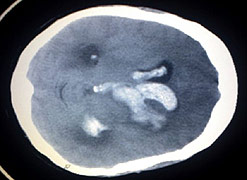

Strokes

Every year about 150,000 people in the UK have a stroke.

Stroke is the third most common cause of death in the UK. It is also a leading cause of severe adult disability. More than 250,000 people live with disabilities caused by stroke.

A stroke is what happens when the blood supply to part of the brain is cut off. Without a blood supply, essential nutrients and oxygen can’t get to the brain’s cells and they become damaged or die.

Strokes are caused either by a blockage, when a clot blocks an artery that carries blood to the brain, or when a blood vessel bursts causing a bleed into the brain.

Tests including scans should be carried out quickly to assess the cause of the stroke. Blood-thinning drugs may be given where a clot is involved.